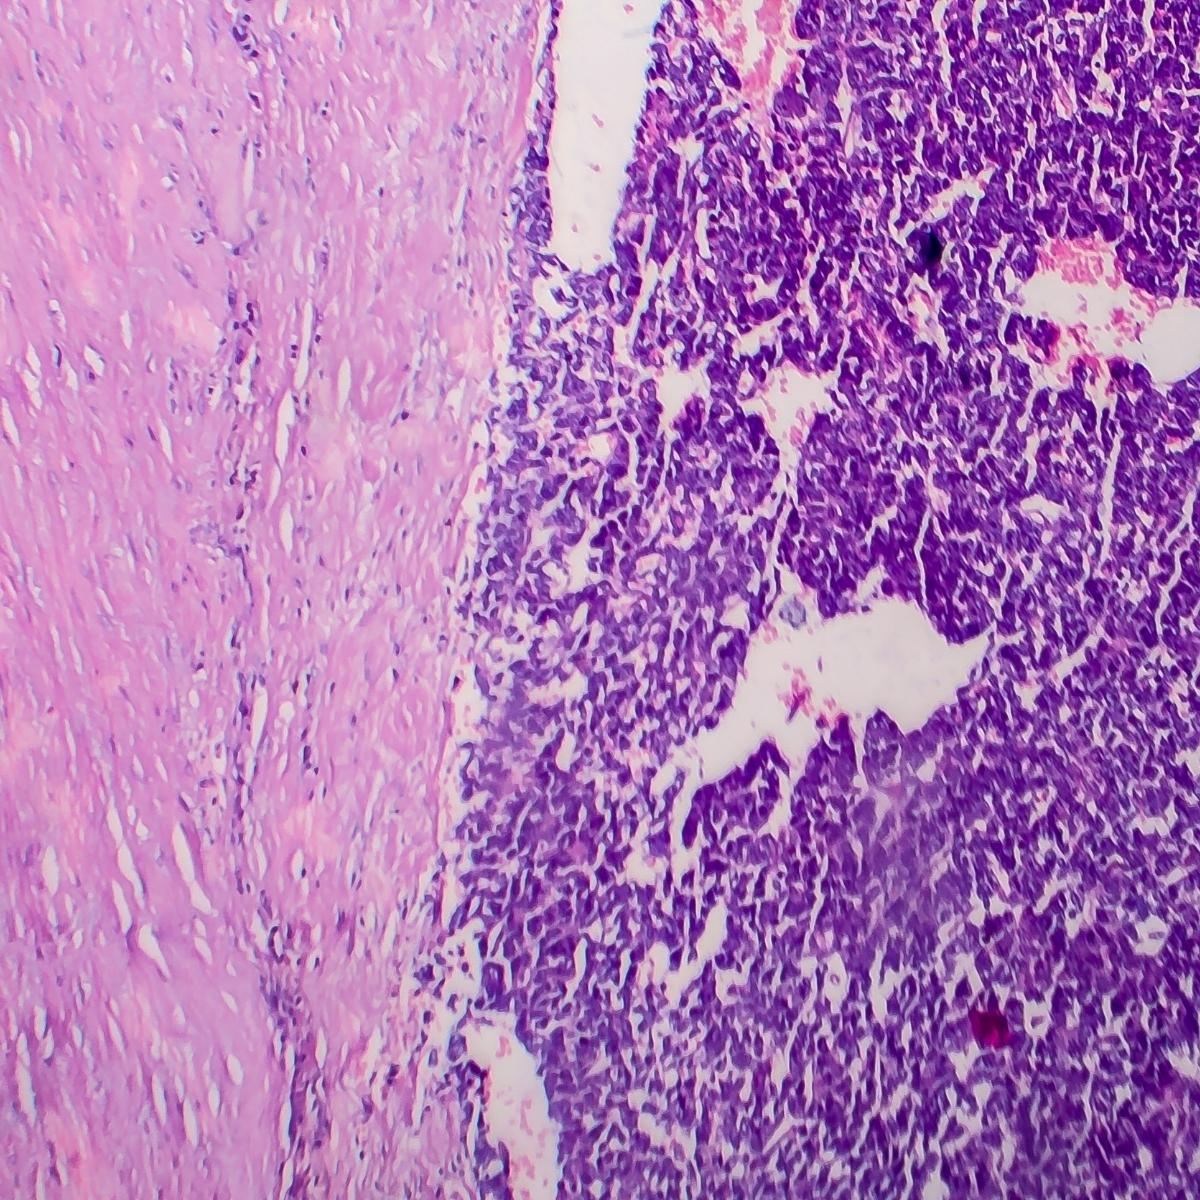

Wilms tumor (Nephroblastoma, Kidney cancer)

The kidneys are bean shaped structures which function as excretory organs of our body. They help in removal of the waste products of metabolism and they also play an essential role in maintenance of homeostatic functions. Wilms tumor is defined as malignant condition of the kidney occurring in children. Cases of wilms tumor is rare in adults. The incidence is peak between the age of 3-5years.Unilateral affection is more commonly seen.